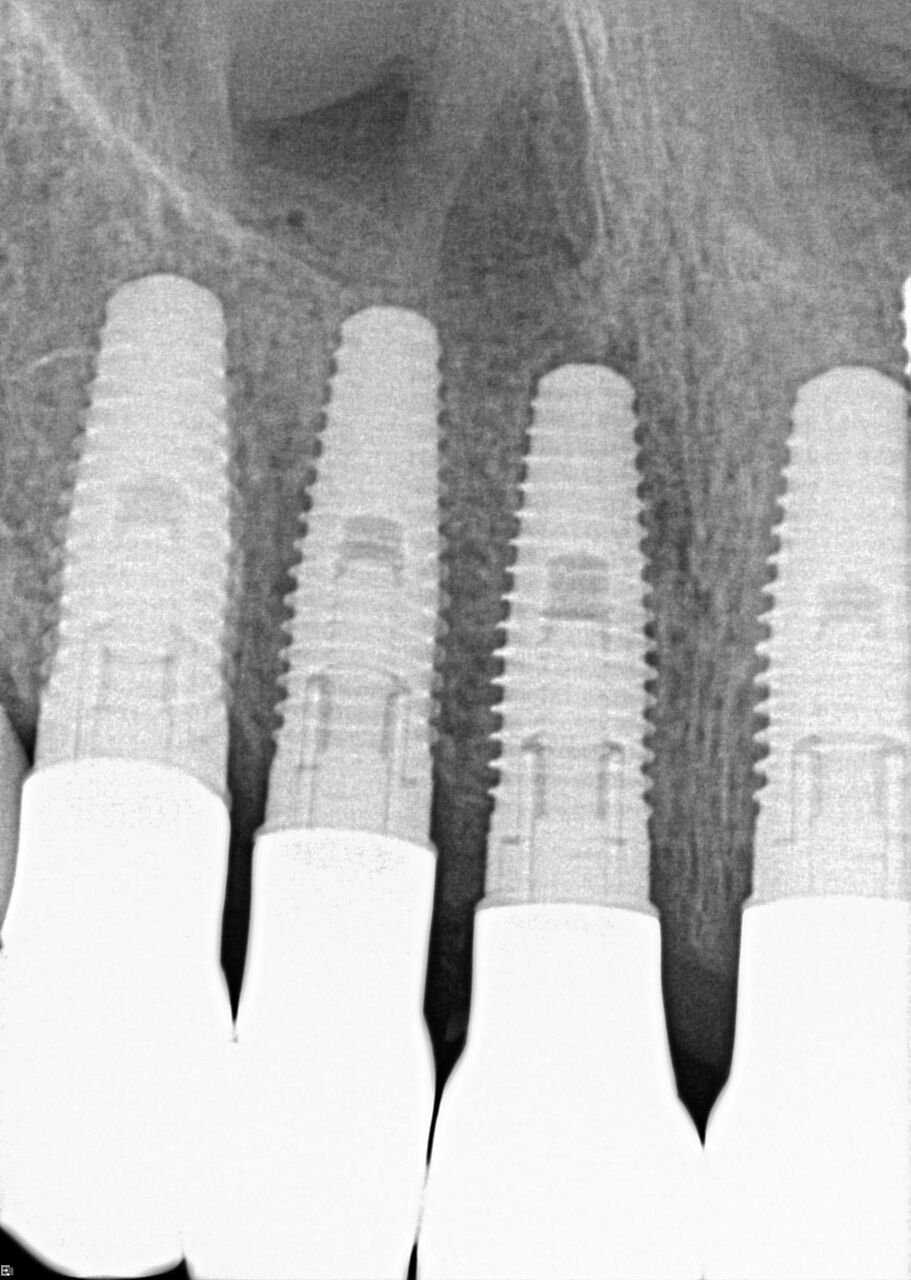

A 42-year-old man presented with a very loose bridge on Nos. 6 through 9 with periodontally compromised retainers on Nos. 6 and 9 (Figure 17 through Figure 19), and endodontically involved No. 10 with a calcified canal. Teeth Nos. 6, 9, and 10 were extracted, the sockets fully debrided, and pontic soft tissue on Nos. 7 and 8 sculpted to be symmetrical in soft tissue contour with the contralateral lateral incisor and central incisor locations. Implants were secured in position Nos. 6 through 10 (Figure 20) in excess of 45 Ncm, the bone was milled to provide unimpeded seating of temporary abutments, and temporary crowns were fabricated chairside and adjusted to be out of occlusion in centric relation and all excursions. The temporary crowns were cemented after extrusion of excess cement extraorally and the patient was prescribed antibiotics, analgesics, and instructed in postoperative care particular to immediately provisionally restored implants. At 6 months, integration was confirmed (Figure 20 through Figure 23) and after placement of scanning abutments, the implants and soft tissues were scanned. Final crowns were fabricated from the scanned images and were cemented after extrusion of excess cement extraorally (Figure 24 through Figure 26), and oral hygiene procedures were reviewed.

(20.) 6-month integration confirmation of Nos. 6 through 10.

Figure 20

(21.) 6-month integration confirmation of Nos. 6 through 10.

Figure 21